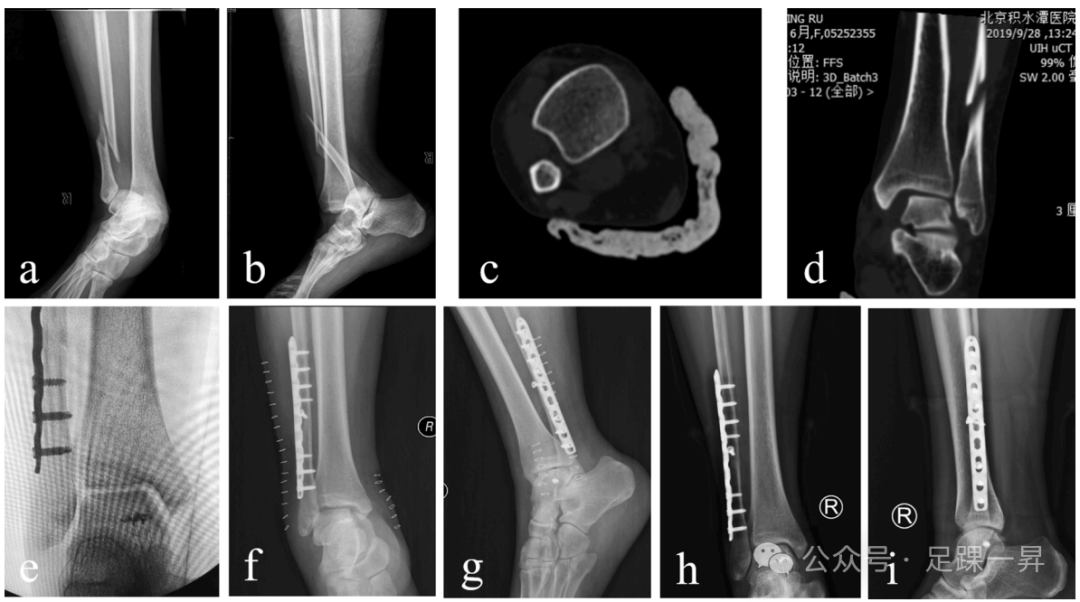

手术均在止血带下仰卧位进行。首先,通过外侧入路,按照标准AO原则,暴露腓骨骨折并进行解剖复位,采用合适长度的锁定钢板固定。随后进行外旋应力试验和拉钩试验,证实三角韧带和下胫腓联合不稳定。若应力试验显示踝关节内侧间隙≥5mm且下胫腓间隙增宽>2mm,则将患者纳入研究。

在内踝中央做一弧形切口,通常可看到破裂的三角韧带浅层,偶见其嵌入内踝骨折间隙。随后,将胫后肌腱向后牵开,踝关节外翻,暴露三角韧带深层。在距骨体内侧三角韧带深层止点中心,平行于距骨穹窿植入1枚2.5mm导针,随后植入5.0mm缝合锚钉。接着,使用1.5mm克氏针,沿三角韧带止点方向,在内踝钻2个斜孔(1个位于丘间沟水平,1个位于后丘)。将与锚钉相连的4根缝线通过这2个孔引出,每个孔2根缝线。最后,将踝关节置于矢状面90°、内翻位,将缝线固定于踝关节内侧胫骨皮质。重复外旋应力试验,检查踝穴完整性及稳定性,最后直接缝合三角韧带浅层。

两组患者术后均采用短腿石膏固定4周,随后允许部分负重及踝关节主动和被动活动度(ROM)训练。完全负重根据患者耐受情况逐步进行。但下胫腓联合固定组患者被告知,在未取出螺钉的情况下负重可能导致螺钉断裂。尽管螺钉断裂很少引起不适,但所有患者均选择在术后10-12周取出螺钉后再开始负重。所有患者在术后1、3、6、12个月定期随访,评估其临床结局、影像学表现及并发症情况。